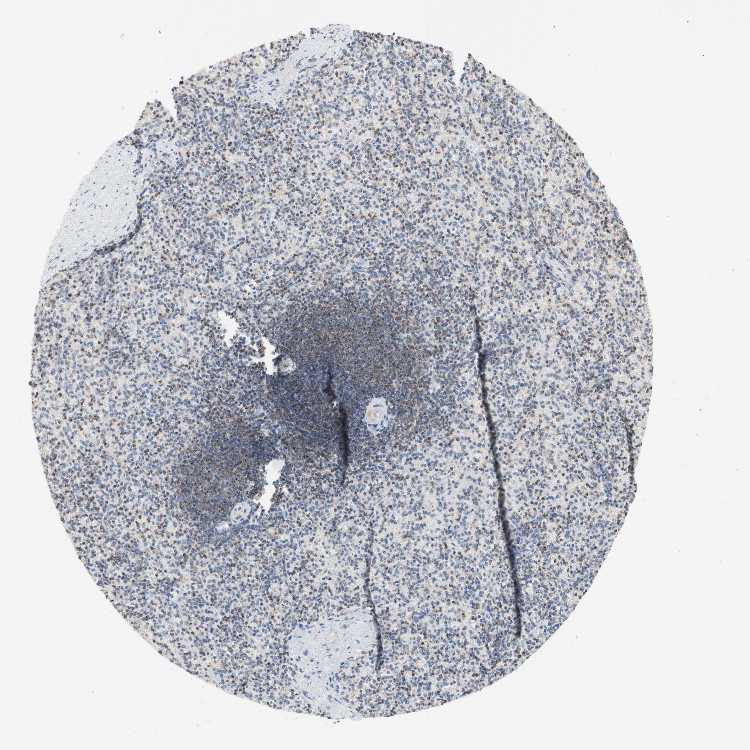

SPLEEN - Antibody stainingi

Antibody staining in the annotated cell types in the current human tissue is reported as not detected, low, medium, or high, based on conventional immunohistochemistry profiling in selected tissues. This score is based on the combination of the staining intensity and fraction of stained cells.

Each image is clickable and will lead to virtual microscopy that enables deeper exploration of all samples and also displays staining intensity scores, fraction scores and subcellular localization as well as patient and tissue information for each sample.

Antibody HPA004868Antibody HPA005729

Cells in red pulp MediumMedium

Cells in white pulp MediumNot detected